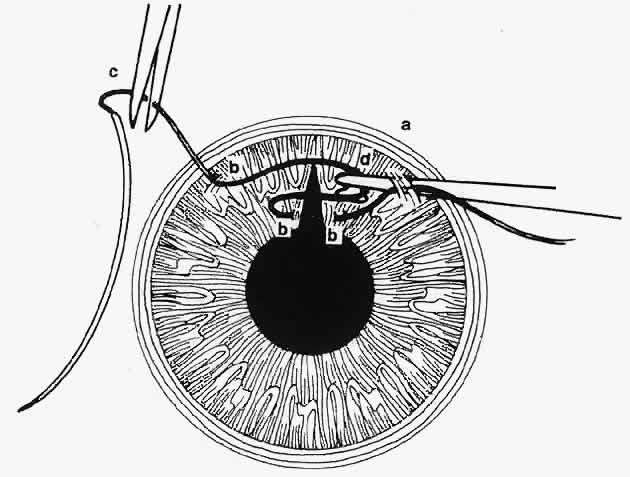

I recently found a very knowledgible doctor who has evaluated my complicated eye condition & is confident he can perform the unique procedures. Medical technology at the time of my initial eye surgeries was less advanced, leaving the anatomy of my eyes as one more challenge today. Without getting into any gory details of this next surgery on April 29th, the plan is to secure a special, artificial, intraocular lens implant, as well as perform a pupilloplasty. I will most definitely need plenty of recovery time.

I recently found a very knowledgible doctor who has evaluated my complicated eye condition & is confident he can perform the unique procedures. Medical technology at the time of my initial eye surgeries was less advanced, leaving the anatomy of my eyes as one more challenge today. Without getting into any gory details of this next surgery on April 29th, the plan is to secure a special, artificial, intraocular lens implant, as well as perform a pupilloplasty. I will most definitely need plenty of recovery time.